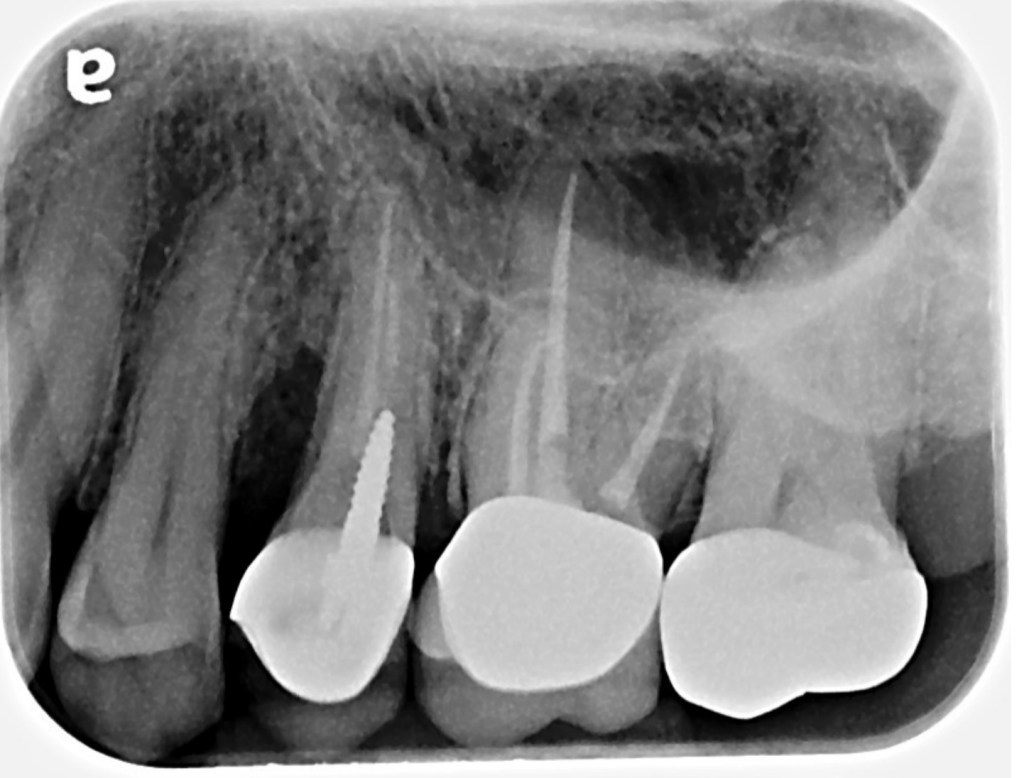

As you can see, 13 is a goner. So I pulled it.

13 was partially in the patient’s smile line so he was very eager to get an implant as soon as possible. For some strange reason, he hated his flipper. Shocking! The problem was that he

had already lost bone because of the vertical root fracture. There was no way that I could tell

that patient, with confidence, that the edentulous area around 13 would be ready for an implant

in only six months without the use of some kind of socket preservation.